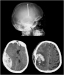

Evidenzbasierte Neurotraumatologie Journal für Neurologie, Neurochirurgie und Psychiatrie 2008; 9 (3): 20-27 Volltext (PDF) Summary Praxisrelevanz Abbildungen Keywords: Neurochirurgie, Neurotraumatologie Evidenzbasierte Medizin bedeutet die individuelle klinische Erfahrung mit der besten verfügbaren Evidenz aus systematischer Forschung zu vereinbaren. In der Neurotraumatologie lassen sich in der Akutphase kaum prospektive randomisierte Studien durchführen. Während der Behandlung von Patienten mit Schädelhirntrauma (SHT) kommt es immer wieder zu alltäglichen Fragestellungen, wie Zeitpunkt des Beginns der Thromboseprophylaxe, antikonvulsive Prophylaxe, Indikation und Art der Hirndruckmessung, Häufigkeit zerebraler CT-Kontrollen, auf die wir uns wissenschaftlich fundierte Antworten wünschen. Ziel dieser Arbeit war es, evidenzbasierte Antworten auf diese Fragen zu finden. Die zu den einzelnen Fragestellungen publizierten Studien wurden in prospektiv-randomisierte, retrospektive Studien und Fallberichte unterteilt. Dementsprechend ließ sich eine Therapierichtlinie bezogen auf spezifische Fragestellungen herausarbeiten. Bei fehlender wissenschaftlicher Grundlage wurden Therapieempfehlungen ausgearbeitet und in einigen Fällen ließ sich nur auf Expertenmeinungen hinweisen. |